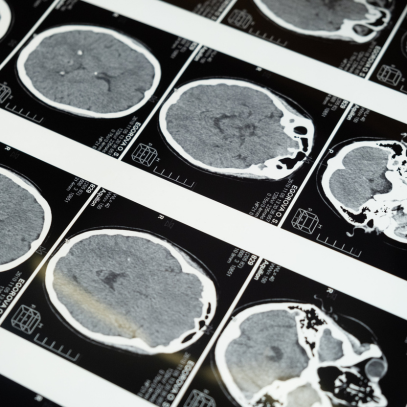

NEWS: Holding Prescribed Aspirin in Chronic SDH Receiving Burr Hole Evacuation May Not Decrease the Risk of Recurrent SDH Requiring Surgical Intervention at 6 Months

Written By: Shannon Hextrum, MD

Background: There is uncertainty regarding whether aspirin should be continued in patients with chronic subdural hematoma (cSDH) who undergo surgical evacuation. The risk of bleeding in the setting of aspirin use should be weighed against the risk of cardiovascular events in the setting of...